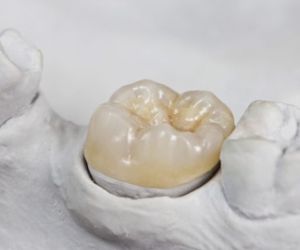

Зубные вкладки

Зубные вкладки или микропротезы - восстановительные, культевые. Материалы изготовления, а также виды зубных микропротезов. Далее в статье р…